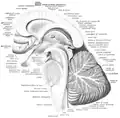

Sección sagital media del tronco encefálico.

Sección sagital media del tronco encefálico. Sección sagital media del tronco encefálico. Arbor vitae etiquetado en el centro.

Sección sagital media del tronco encefálico. Arbor vitae etiquetado en el centro. Sección sagital del tronco cerebral.